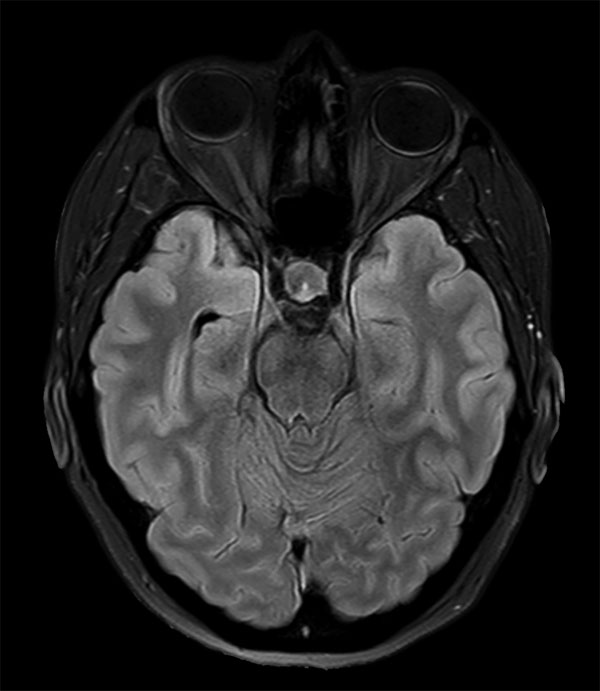

Subtle 4mm focus of decreased enhancement in the right pituitary posteriorly. No definite discrete lesion is demonstrated and the findings are equivocal for a microadenoma. Follow up imaging with MRI in six months is indicated. No suprasellar lesion or no other intracranial abnormality is demonstrated.

Axial T2w FLAIR